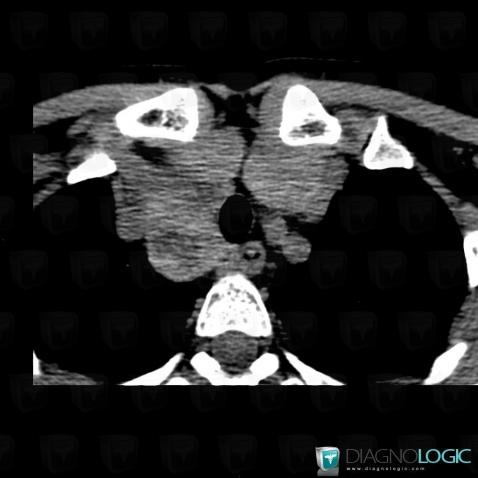

Goiter, Mediastinum, CT

Here is the specific information in the key image above:

- Diagnosis Goiter, Location(s) Mediastinum, with gamuts Superior mediastinal mass, Anterior mediastinal mass